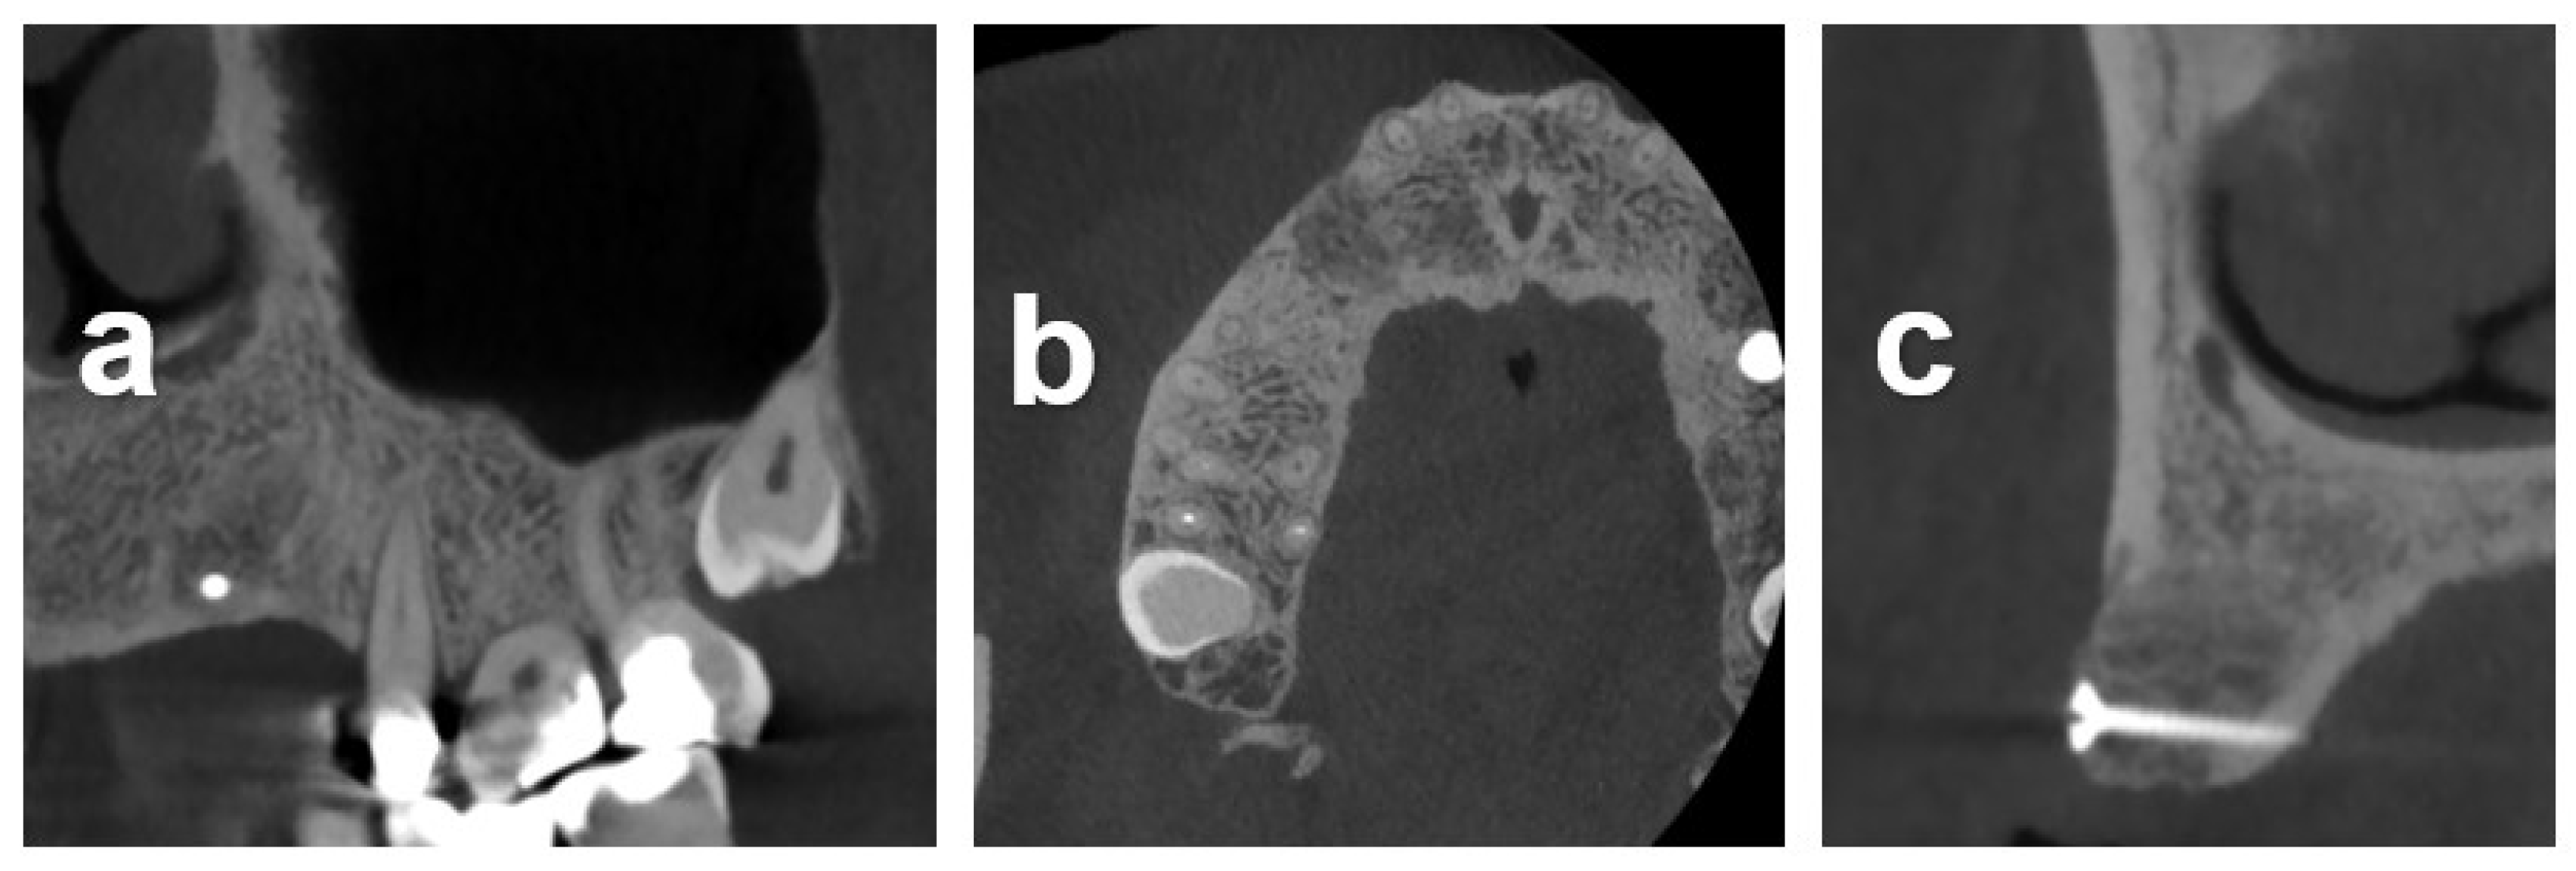

2.7.3. Case 3